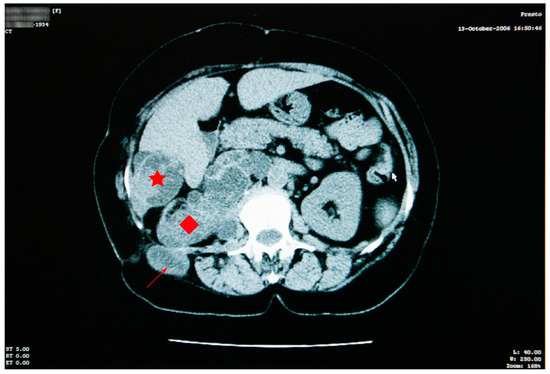

A favorable evolution of the cysts under antiparasitic treatment was observed in October 2009 and March 2010 (Figure 4).

The abdominal CT scan showed multiple spontaneous hypodense masses with hyperdense borders, occupying the entire kidney space, with no evidence for the right kidney (Figure 6).

The maximum axial dimension of the above-mentioned lesions was 10 cm, which is considerably less than what was recorded in 2006. In addition, this conglomerate of hypodense images was remarked to have increased in overall density. The conglomerate presented cranial and caudal extension, starting just beneath the diaphragm and ending right under the plane of the renal artery, with a close anatomic relation to the right diaphragm pillar, right hemidiaphragm, and right psoas muscle. The spontaneous hypodense, heterogenous mass, with an axial maximum diameter of 46 mm, located in the VI liver segment, appeared to be reduced in comparison to the 2006 examination.

Figure 6. Abdominal CT shows reduction in the aspect and dimensions of the cysts—right kidney space (red diamond), the sixth right liver segment (star) and in the right iliac fossa and right paravertebral area (arrow)—associated with favorable evolution under treatment.